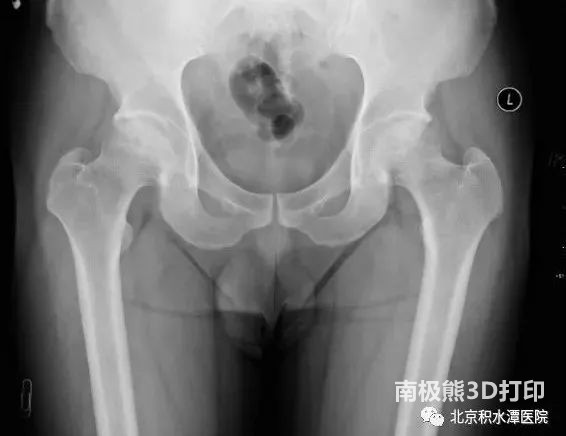

本次进行手术的两名患者均为年轻男性,其中小昭(化名)仅20岁左右,还是父母的心头肉。门诊通过髋关节X光,CT及MRI检查发现,小昭髋关节股骨头坏死,坏死区已经塌陷,但关节间隙正常,尚无明显骨关节炎表现。同时患者年轻,要求尽可能保留健康骨质。周一新教授团队通过对病情的综合判断,除了提供全髋置换等传统治疗选择之外,给了患者另一个选择——定制部分髋关节置换术。在充分沟通各种治疗选择的优劣后,小昭及家属决定选择定制部分髋关节置换术这一创新术式。

▲患者术前影像学资料显示右股骨头坏死,坏死区部分塌陷,但关节间隙正常,尚无明显骨关节炎。